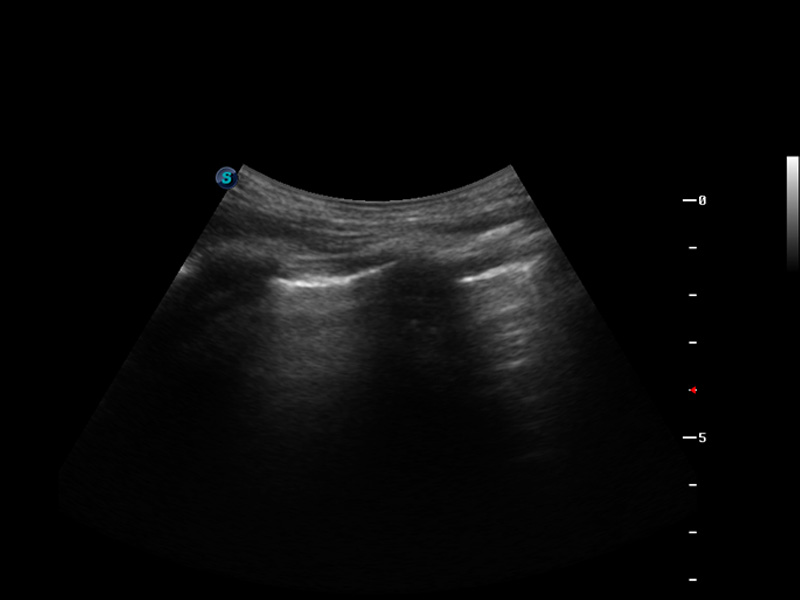

S9便携式彩色多普勒超声诊断仪是1xBET研发的高端便携彩超设备,外观设计新颖、产品性能卓越。S9在便携超声领域采用了突破传统的触摸屏交互设计,并以先进的软件硬件技术和设计理念,为您带来清晰的图像质量、稳定的工作性能和便捷的操作体验。

μ-Scan微米成像